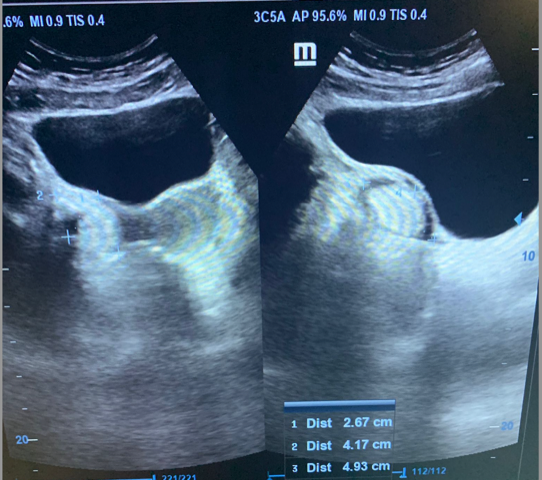

Casos:

1. Mujer de 62 años; distensión abdominal; carcinoma de ovario.

2. Mujer de 46 años; dolor abdominal; masa ovárica a estudio.

3. Mujer 19 años; asintomática, ecografía durante curso de formación; hamartoma.

4. Mujer 32 años; dolor abdominal; quiste ovárico simple.

5. Mujer 27 años; ITU de repetición; ovario poliquístico.